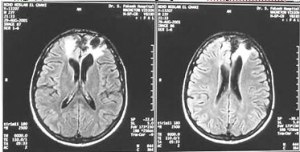

encephalomalaciaWe went back for the results of all the testing and he said, “No tumors showed up at all. But there is significant damage on Bill’s frontal lobe…which of course we knew, but it is quite a large area.” He was surprised at how Bill was functioning on such a high level with the substantial damage that was evident on the scan. Then he said there was “white tissue” surrounding the injury. The way he explained this is that as we age our brains soften, add into the mix a traumatic injury and the tissue surrounding the injury degenerates more quickly. It is called encephalomalacia, and it can cause the symptoms we had observed. It is only surrounding the injured area, meaning that that part of the brain is the only part affected. “This will cause regression back to his head injured state since it is around the same area of the brain. How far, we do not know, but it is an age related condition that cannot be stopped.”